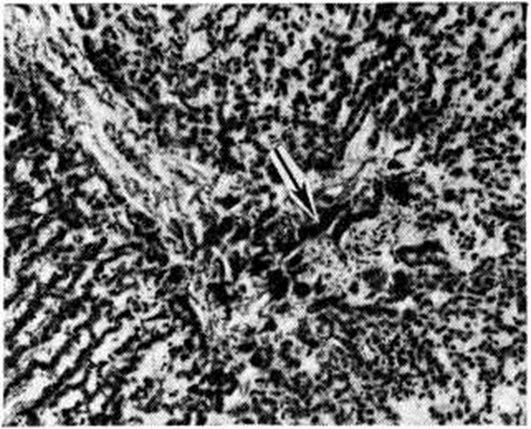

При микроскопическом исследовании костного мозга (смотри полный свод знаний) выявляется различная степень его опустошения. В случае аплазии в жировом костном мозге находят лишь небольшие скопления лимфоцитов, плазматических клеток и недифференцированных элементов, единичных гранулоцитов и нормобластов. При гипоплазии несколько чаще обнаруживают участки кроветворной ткани. Характерна неравномерность распространения очагов кроветворения не только в различных участках скелета, но и в пределах одной и той же кости. Структура костной ткани чаще сохранена. Как для ранних, так и для поздних фаз болезни характерно отложение гемосидерина в селезёнке, печени (рисунок 1) и костном мозге, реже в почках (рисунок 2), лимфатических, узлах. К частым осложнениям Гипопластическая анемия относят фибринозно-геморрагические пневмонии и некротические изменения в слизистых оболочках и серозных покровах, коже, внутренних органах. Течение и симптомы. Заболевание может протекать остро, подостро или хронически. В острых случаях процесс начинается с бурного геморрагического диатеза (смотри полный свод знаний Геморрагические диатезы), тяжёлой общей интоксикации, инфекционных осложнений. Чаще наблюдается постепенное нарастание симптомов. Появляются адинамия, слабость, головокружение, быстрая утомляемость, одышка при физ. нагрузке, иногда боли в костях и области сердца. Отмечается восковидная бледность кожи без желтушности, малокровие видимых слизистых оболочек. Подкожная жировая клетчатка сохранена. При развитии глубокой тромбоцитогонении (смотри полный свод знаний) возникают кровоизлияния на коже, слизистых оболочках и глазном дне, носовые, десневые, маточные, кишечные, почечные и другие кровотечения. При прогрессировании процесса может иметь место неврологический симптоматика, обусловленная геморрагиями в головной мозг. При парциальной Гипопластическая анемия кровоточивость отсутствует. Размеры лимф, узлов, селезёнки и печени не изменяются. Картина крови. Анемия носит нормохромный, нормоцитарный, реже макроцитарный характер. Полихроматофилия отсутствует, число ретикулоцитов нормально или снижено. Лейкопения может достигать 1000 клеток в 1 микролитров. и менее; она обусловлена в основном гранулоцитопенией и сопровождается относительным лимфоцитозом. Абсолютное число лимфоцитов при резкой лейкопении также снижено. Отмечается тромбоцитопения с удлинением времени кровотечения (смотри полный свод знаний) и снижением ретракции кровяного сгустка (смотри полный свод знаний Ретракция). Плазменные факторы свёртывания крови (смотри полный свод знаний Свёртывающая система крови) не изменяются. Содержание сывороточного железа повышено, общая железо-связывающая способность сыворотки чаще повышена. Парциальная Гипопластическая анемия характеризуется хронический нормоцитарной анемией, часто без лейко- и тромбоцитопении, с глубокой ретикулоцитопенией. Пунктат костного мозга, как правило, скудный, ядерные элементы представлены в основном лимфоцитами, немногочисленными гранулоцитами и нормобластами. Мегакариоциты чаще отсутствуют. Иногда, несмотря на явную панцитопению, пунктат оказывается довольно богатым; это связано с попаданием иглы в очаг сохранившегося кроветворения. Помимо чисто количественного дефицита эритробластических элементов, при Гипопластическая анемия отмечают признаки качественной их патологии (дизэритропоэз), мегалобластоидность, атипичные митозы, многоядерность (смотри полный свод знаний Дизэритропоэтическая анемия). При парциальной Гипопластическая анемия пунктат костного мозга богат ядерными элементами, лейкотромбоцитопоэз не нарушен, но число клеток красного ряда нередко резко уменьшено или они полностью отсутствуют. Трепанобиопсия подвздошной кости выявляет резкое преобладание жирового костного мозга над кроветворным (рисунок 3), иногда отсутствие последнего. Исследование с радиоактивным железом 59Fe даёт наиболее точную суммарную оценку эритропоэза: клиренс изотопа из плазмы замедлен, он накапливается в основном в печени, включение метки в эритроциты резко замедлено. Осложнения. Основными осложнениями и непосредственной причиной смерти больных являются кровотечения и инфекционно-воспалительные процессы. Геморрагии выявляются при снижении числа тромбоцитов ниже критического уровня (20 000—30 000 в 1 микролитров.), могут провоцироваться даже незначительными травмами (подкожные инъекции и так далее). Инфекции (пневмонии и другие) развиваются при достаточно длительном и выраженном (менее 500 в 1 микролитров.) снижении числа нейтрофилов. Всякая лихорадка у больных Гипопластическая анемия, как правило, связана с наличием инфекционного очага; описано немало случаев развития у них острого лейкоза. Лейкозы на фоне гипоплазии лучевого или бензольного происхождения относятся к группе миелобластных или миеломонобластных и являются, видимо, поздним результатом лейкемогенного действия фактора, вызвавшего анемию. Значительно реже наблюдается присоединение к Гипопластическая анемия пароксизмальной ночной гемоглобинурии, хотя некоторые авторы трактуют в этих случаях Гипопластическая анемия как гипопластическую стадию данной формы гемолитической анемии. Диагноз основывается на наличии панцитопении и бедного ядерными клетками пунктата или трепаната костного мозга при отсутствии увеличения лимф, узлов, селезёнки и печени. Гипопластическая анемия следует дифференцировать главным образом с панцитопениями другого происхождения. Обнаружение в крови молодых клеток белого или красного ряда, даже незначительное увеличение селезёнки всегда должны вызывать сомнение в диагнозе Гипопластическая анемия. В этих случаях можно предположить наличие алейкемических форм лейкозов (смотри полный свод знаний), раковых метастазов в костный мозг, миеломной болезни (смотри полный свод знаний). Диагноз обычно ставят на основании исследования пунктата костного мозга; миеломной болезни, кроме того, присущи характерные изменения белков сыворотки и (или) мочи. Панцитопения при миелофиброзе (смотри полный свод знаний Остеомиелофиброз) сопровождается, в отличие от Гипопластическая анемия, увеличением и миелоидной метаплазией селезёнки. Анемию Аддисона — Бирмера (смотри полный свод знаний Пернициозная анемия) отличает от Гипопластическая анемия наличие глоссита, неврологический нарушений, ахлоргидрии, выраженного мегалобластоза костного мозга, хорошего терапевтического эффекта от витамина В12. Диагноз пароксизмальной ночной гемоглобинурии даже в её ранней, гипопластической, стадии подтверждается положительными результатами сахарозной и кислотной проб (смотри полный свод знаний Гемолитическая анемия). При подостром варианте лимфогранулематоза (смотри полный свод знаний) панцитопения сопровождается лихорадкой, нет резкого лимфоцитоза, в трепанате костного мозга иногда удаётся обнаружить клетки Березовского — Штернберга. Панцитопения вследствие гиперспленизма сопровождается, как правило, увеличением селезёнки. ЛечениеМетодов радикального излечения Гипопластическая анемия не существует, однако лечебный мероприятия способствуют удлинению продолжительности жизни больных. При выявлении этиологического фактора необходимо прекратить дальнейшее его воздействие. Для борьбы с анемией показаны трансфузии крови или эритроцитарной массы; эта мера не должна преследовать цель полной нормализации показателей красной крови — достаточно поддержание их на уровне, совместимом с сердечно-сосудистой компенсацией. Число трансфузий должно быть минимальным для уменьшения опасности трансфузионного сидероза (при переливании 450 миллилитров крови в организм вводится 200—250 миллиграмм железа), гепатита и других осложнений. Во избежание изосенсибилизации антигенами лейкоцитов и тромбоцитов целесообразно переливать отмытые эритроциты. При многократных гемотрансфузиях нередко развитие изосенсибилизации антигенами эритроцитов; в этих случаях кровь для трансфузии подбирают по непрямой пробе Кумбса (смотри полный свод знаний Кумбса реакция). В случае сочетания анемии с геморрагическим диатезом показаны переливания свежецитратной крови или прямые гемотрансфузии в разовой дозе не менее 500 миллилитров. Более выраженным гемостатическим эффектом обладают тромбоцитарные концентраты, получаемые с помощью сепаратора клеток крови от одного донора или путём центрифугирования большого числа доз крови, взятых от различных доноров. Кровоостанавливающее действие тромбоконцентратов проявляется в том случае, если число тромбоцитов у больного удаётся повысить хотя бы до 15 000 —20 000 в 1 микролитров. крови. При многократных переливаниях тромбоцитарных концентратов, особенно полученных из крови разных доноров, неизбежно развивается изосенсибилизация к тромбоцитарным антигенам и отмечается снижение терапевтической эффективности трансфузий. Поэтому желательно в качестве доноров использовать ограниченное число лиц, лучше родственников, максимально совместимых по антигенам системы HL — А (смотри полный свод знаний Группы крови, лейкоцитарные антигены). Среди лекарственных препаратов свойством стимулировать эритропоэз обладают лишь анаболические стероиды (смотри полный свод знаний). Необходимым условием достижения терапевтического эффекта считают длительность применения гормонов в достаточно высокой дозе (например, метилтестостерон или неробол по 1 — 2 миллиграмм на 1 килограмм веса тела в день внутрь в течение 3—4 месяцев) [Мак-Креди (К. В. Mc-Credie), 1969]. Первым проявлением лечебный эффективности препаратов может быть улучшение показателей периферической крови. При появлении признаков побочного действия (задержка жидкости, поражение печени) гормоны отменяют. Для лечения Гипопластическая анемия применяют также кортикостероиды (преднизолон 0,5—1,0 миллиграмм на 1 килограмм веса тела или эквивалентные дозы других стероидов) главным образом с целью гемостатического действия (понижение сосудистой проницаемости); для этого используют и другие, так называемый сосудоукрепляющие средства — аскорбиновую кислоту, рутин, препараты кальция. С целью уменьшения гемосидероза органов и тканей можно назначать препараты типа десферала. Многочисленные попытки пересадки больным донорского костного мозга, предпринимавшиеся без должного иммунологический подбора (только по основным эритроцитарным антигенам), оказались безуспешными, то есть завершились отторжением трансплантата вследствие биол. несовместимости. Случаи подлинной трансплантации немногочисленны. Томас (Е. D. Thomas) с сотрудники (1974) осуществили у четырёх больных Гипопластическая анемия успешную пересадку сингенного костного мозга, полученного от однояйцевых близнецов больных, приведшую к полному выздоровлению; операция проводилась без специальной подготовки ввиду антигенной идентичности реципиентов и доноров. Однако подобная возможность является казуистической. Аллогенные пересадки (от доноров, совместимых по системе Н1—А) требуют сложной подготовки реципиентов для предотвращения отторжения трансплантата (общее облучение или введение циклофосфана с целью иммунодепрессии), а также послеоперационного применения цитостатиков для подавления иммунологический реакции «трансплантат против хозяина» (смотри полный свод знаний Несовместимость иммунологическая). Из 24 больных Гипопластическая анемия, описанных Томасом с сотрудники, 12 прожили свыше 3 месяцев; приживление у них трансплантата было доказано в результате анализа полового хроматина (смотри полный свод знаний). У больных, получивших ранее многочисленные гемотрансфузии, шансы на приживление трансплантата в связи с образованием изоантител снижаются. Сложность методики пересадки костного мозга делает ее доступной лишь для отдельных специализированных учреждений. Вопрос об эффективности спленэктомии окончательно не решён. При выраженных геморрагиях операция противопоказана в связи с высокой летальностью. Вероятно, более целесообразна спленэктомия (смотри полный свод знаний) у больных с повышенной секвестрацией тромбоцитов и эритроцитов в селезёнке, доказанной радиоизотопным методом, и при сохранности очагов нормального кроветворения в костном мозге. ПрогнозПрогностически неблагоприятным признаком считают острое начало болезни. Формы с острым течением обычно устойчивы к терапии и через несколько недель заканчиваются смертью. Чаще течение болезни затяжное, многомесячное и даже многолетнее. Возможно длительное отсутствие клин, проявлений заболевания, однако у больных сохраняются признаки неполноценного костномозгового кроветворения. ПрофилактикаЛица, профессионально связанные с воздействием миелотоксических факторов (источники ионизирующей радиации, бензольное производство), должны находиться под постоянным диспансерным наблюдением. Проведение цитостатического лечения по поводу опухолей и других заболеваний требует регулярного контроля состава крови и своевременного прекращения при угрозе гипоплазии кроветворения. Применение потенциально опасных препаратов, в первую очередь левомицетина (смотри полный свод знаний), должно быть ограничено прямыми показаниями и находиться под контролем состава крови. Профилактика геморрагий при уже развившейся Гипопластическая анемия включает гормональное подавление менструального цикла у женщин с массивными меноррагиями, замену (по возможности) инъекционных лечебный препаратов пероральными, щажение слизистых оболочек (исключение грубой пищи, замена жёстких зубных щёток ватными тампонами). Для предотвращения инфекционных осложнений при глубокой гранулоцитопении (смотри полный свод знаний Лейкопения) рекомендуется подавление кишечной аутофлоры неабсорбируемыми антибиотиками, больных следует содержать в асептических или близких к ним условиях, следить за соблюдением личной гигиены. Гипопластическая анемия у детей. Приобретённые формы Гипопластическая анемия у детей протекают так же, как у взрослых. Наряду с ними в детском возрасте встречаются и некоторые врождённые (конституциональные) формы болезни. Анемия Фанкони (синонимы: синдром Фанкони, врождённая панцитопения). Описана в 1927 год под названием «семейная детская пернициозоподобная анемия». С тех пор опубликовано около 200 наблюдений. Анемия, как правило, выявляется в первые годы жизни, изредка позже. Мальчики болеют в 2 раза чаще девочек. Характерно сочетание панцитопении и гипоплазии костного мозга с другими врождёнными дефектами — коричневой пигментацией кожи в связи с отложением меланина, атрофией почек и селезёнки, отсутствием или недоразвитием 1 пястной или лучевой костей, задержкой умственного, физ. и полового развития, микроцефалией, микроофтальмией. При культивировании лимфоцитов и фибробластов кожи больных выявляются многочисленные хромосомные аберрации. У родственников больных часто отмечают лейкозы. Лечение — назначают систематические переливания крови (эритроцитарной массы). Прогноз неблагоприятный. Семейная гипопластическая анемия Эстрена — Дамешека впервые была описана в 1947 год. Ей свойственны те же изменения со стороны кроветворения, которые наблюдаются при анемии Фанкони, но аномалий развития скелета и внутренних органов не наблюдается. Врождённая парциальная гипопластическая анемия Джозефса — Даймонда — Блекфена описана в 1936 год Джозефсом (W. Н. Josephs) и в 1938 год Даймондом и Блекфеном (L. К. Diamond, К. D. Blackfan). Генетический дефект, лежащий в основе болезни, не выяснен. Развитие болезни у нескольких детей, родившихся от разных матерей, но от одного отца, свидетельствует о доминантном характере наследования. Развёрнутая картина болезни обычно обнаруживается уже на 1-м году жизни: анемия различной степени сочетается с глубокой эритро- и нормобластопенией на фоне уменьшения количества миелокариоцитов (на начальных этапах развития болезни количество миелокариоцитов костного мозга может быть не изменено). У части больных выявляют другие врождённые дефекты (задержка полового и физических развития), но аномалии развития почек не встречаются. Вследствие многократных гемотрансфузий нередко развивается гемосидероз с портальным циррозом печени (смотри полный свод знаний Циррозы печени). Лечение — систематические переливания крови (эритроцитарной массы) в сочетании с кортикостероидными гормонами и витамином В12. При помощи систематических гемотрансфузий удавалось довести больных детей до 8—15 лет, после чего наступало спонтанное улучшение. Смотри также Анемия.